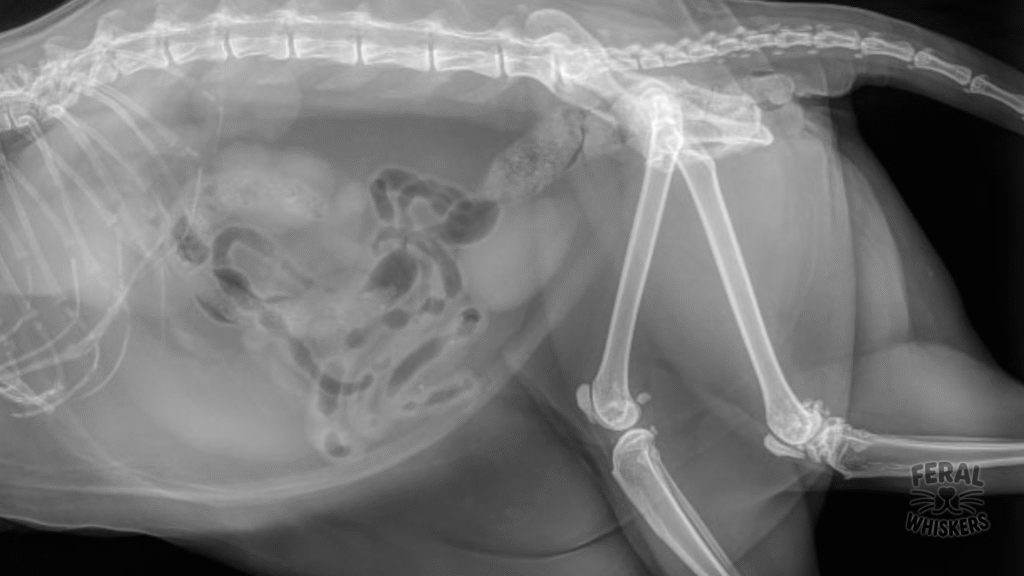

- X‑rays: Reveal bone spurs, cartilage loss, and joint space narrowing.